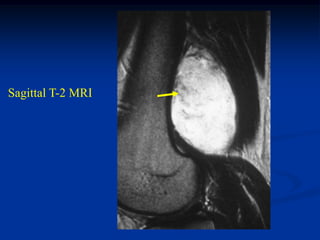

Case #1211.3                        Synovial hemangioma knee

68 year old female with soft mass medial knee for years

Cor T-1    T-2

Gad

Sag PD   Gad

Axial T-2   Gad